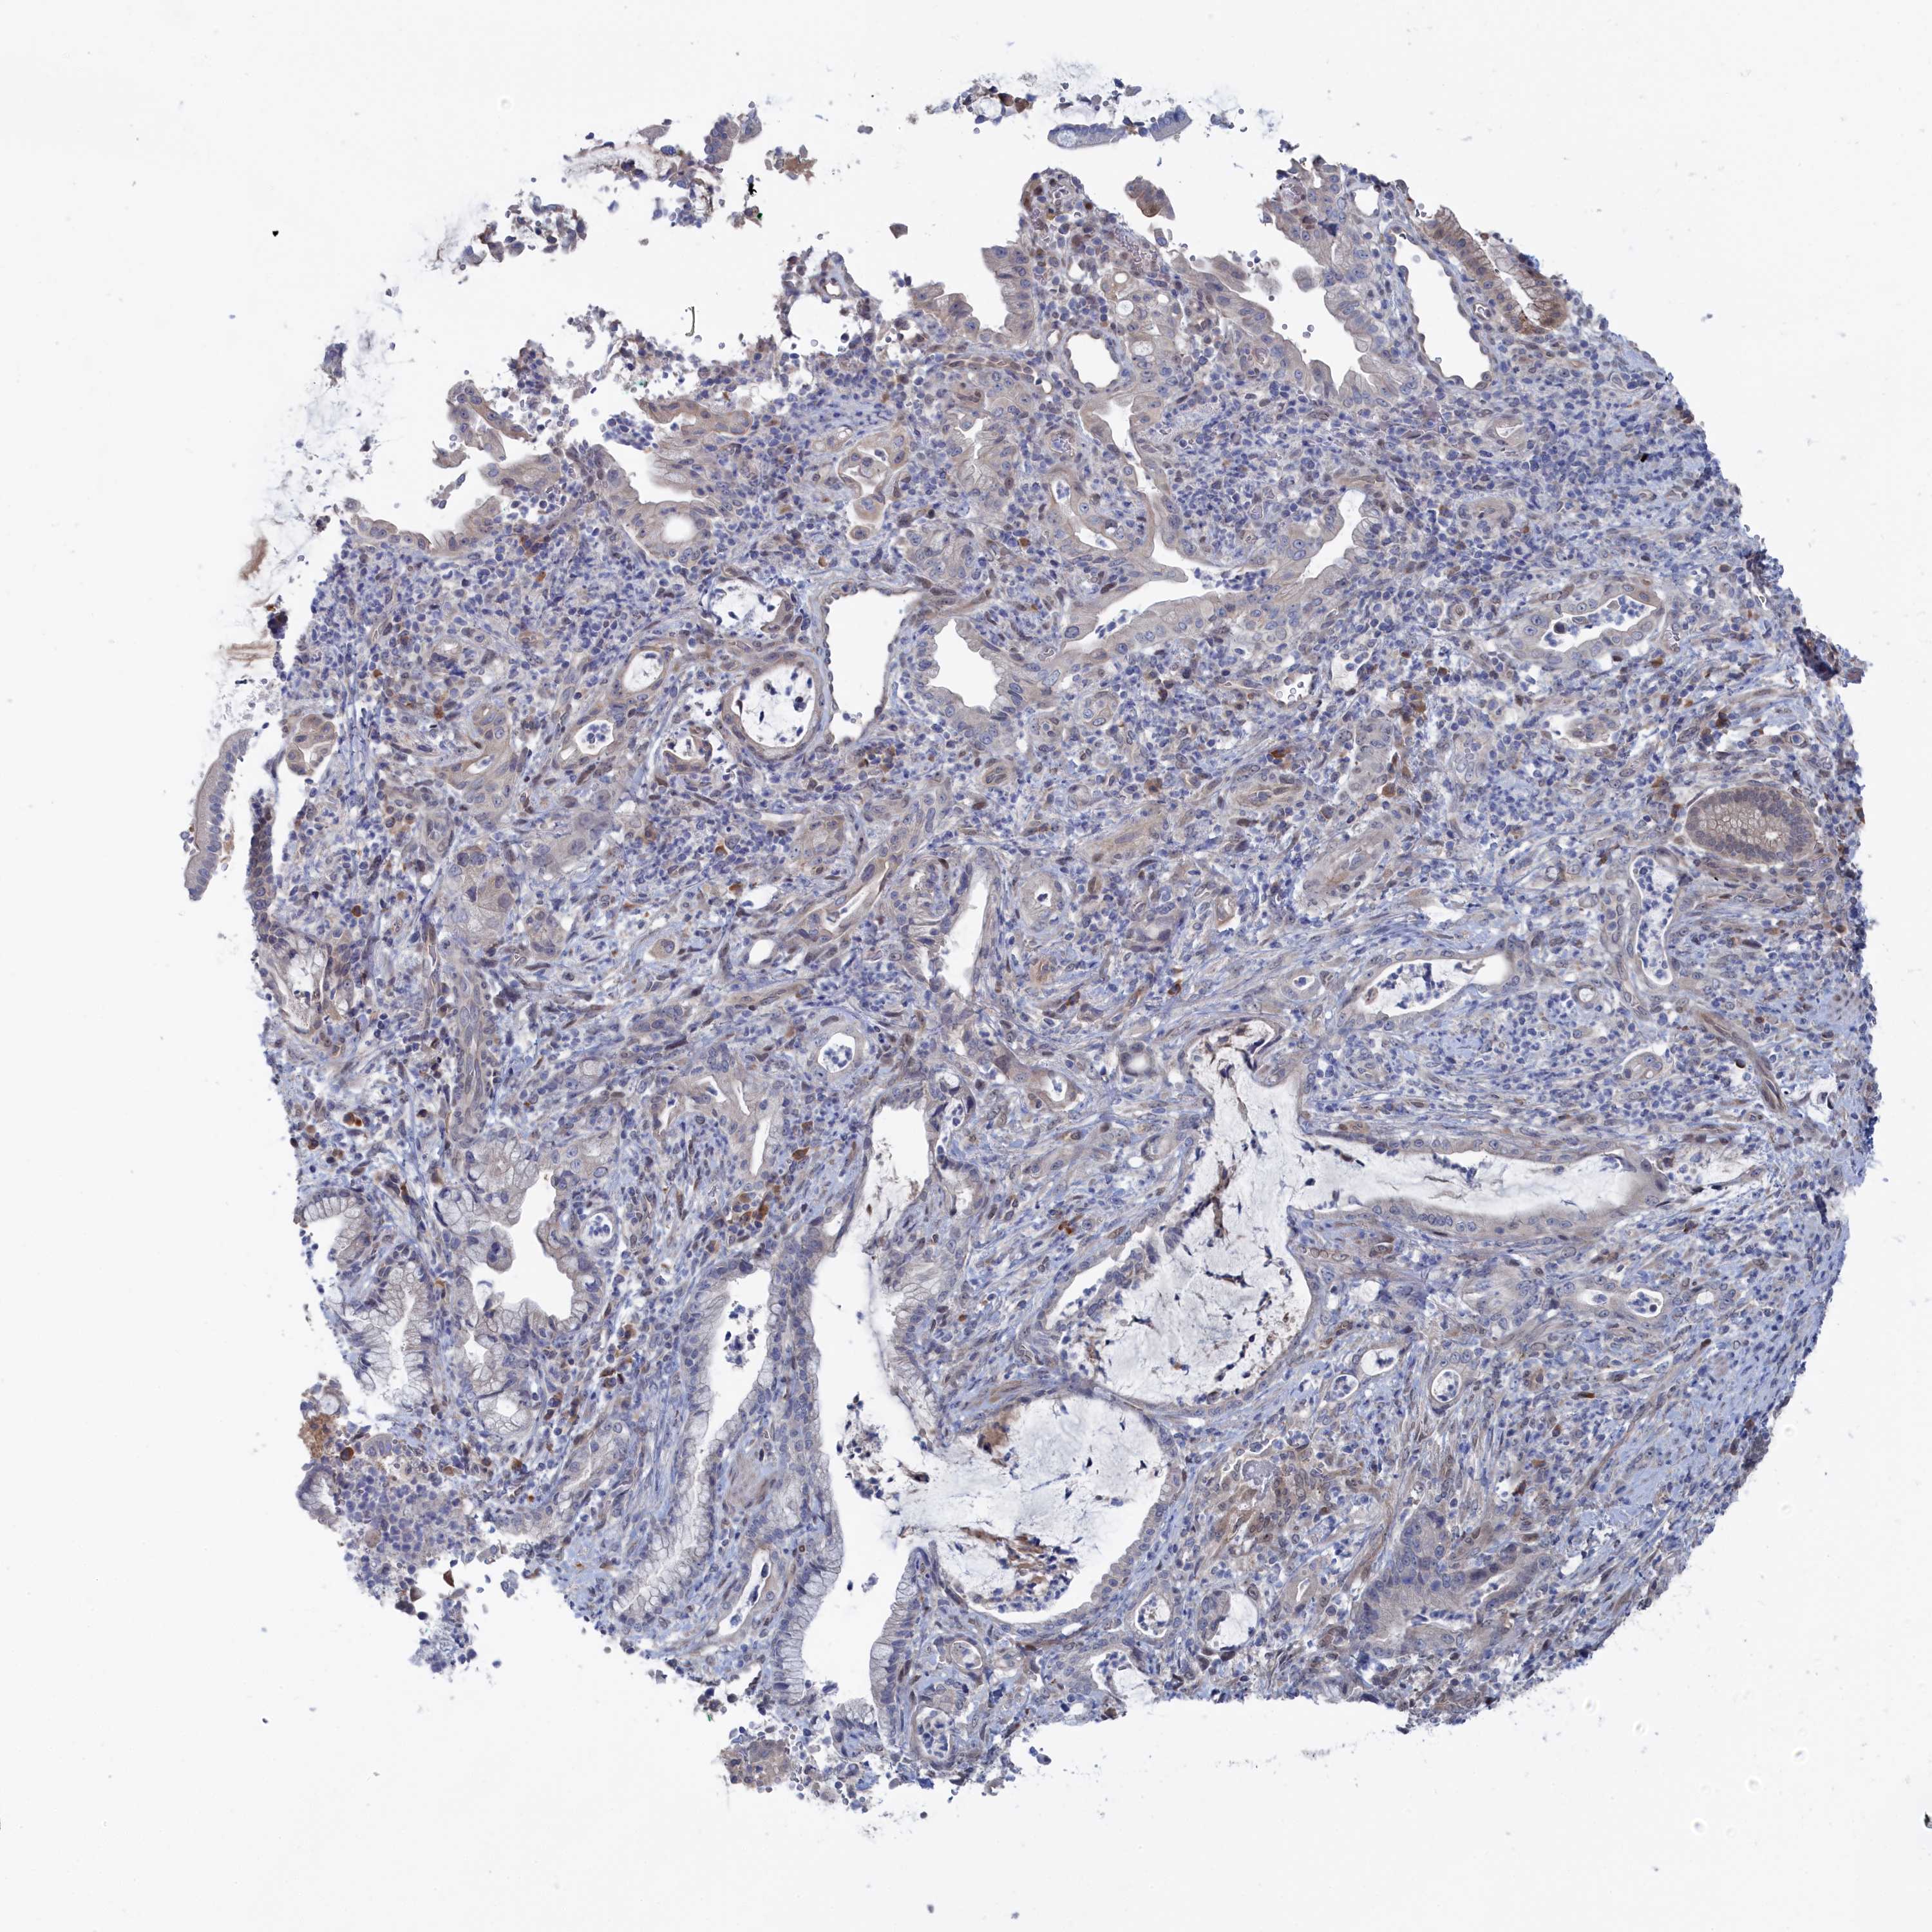

PANCREATIC CANCER - Protein expressioni

A mouse-over function shows sample information and annotation data. Click on an image to view it in a full screen mode. Samples can be filtered based on level of antibody staining by selecting one or several of the following categories: high, medium, low and not detected. The assay and annotation is described here.

Note that samples used for immunohistochemistry by the Human Protein Atlas do not correspond to samples in the TCGA dataset.

Antibody stainingi

Antibody staining in the annotated cell types in the current human tissue is reported as not detected, low, medium, or high, based on conventional immunohistochemistry profiling in selected tissues. This score is based on the combination of the staining intensity and fraction of stained cells.

Each image is clickable and will lead to virtual microscopy that enables deeper exploration of all samples and also displays staining intensity scores, fraction scores and subcellular localization as well as patient and tissue information for each sample.

Antibody HPA043254

Staining

High

Medium

Low

Not detected

Intensity

Strong

Moderate

Weak

Negative

Quantity

>75%

75%-25%

<25%

None

Location

Nuclear

Cytoplasmic/membranous

Cytoplasmic/membranous,nuclear

Adenocarcinoma, NOS